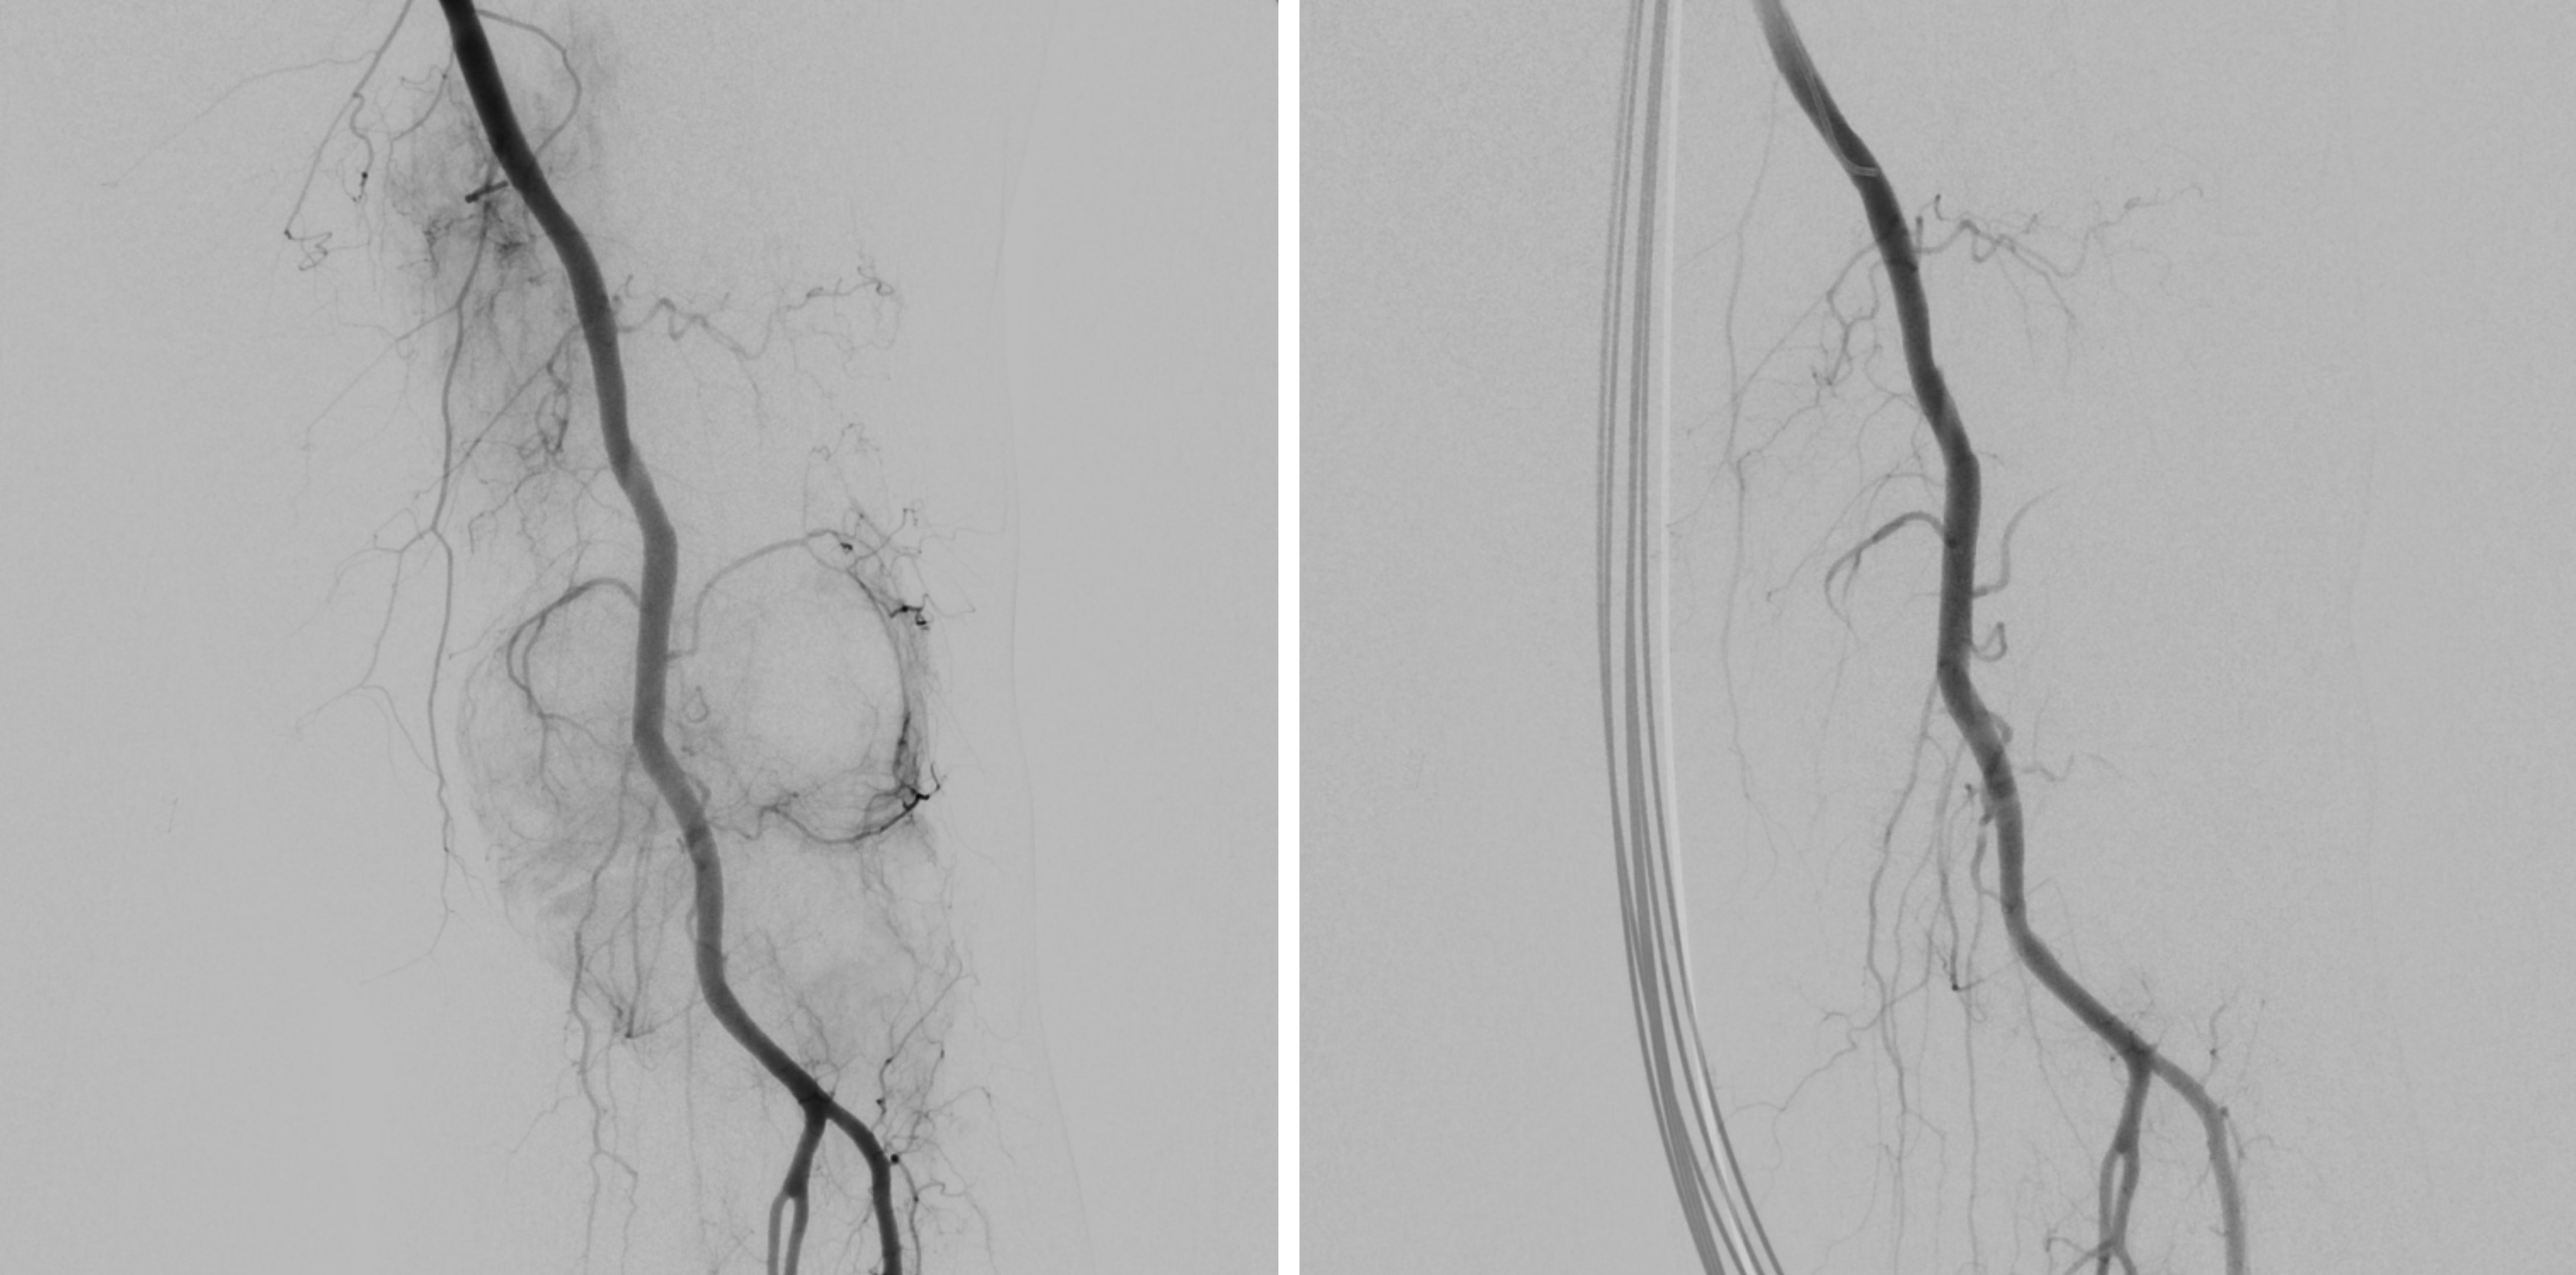

Alternativ zur offenen chirurgischen Therapie eines Aortenaneurysmas besteht die Möglichkeit einer endovaskulären Aneurysmaausschaltung mittels eines Stentgrafts (gewebeummanteltes Metallgittergeflecht). Voraussetzung für die endovaskuläre Therapie ist jedoch eine anatomische Eignung, welche eine ausreichende Weite der Beckengefäße und nötige Verankerungszonen für den Stentgraft mit sich bringt. Die Stentgraft Implantation wird von Interventionellen Radiologen in Zusammenarbeit mit Anästhesist:innen und Gefäßchirurg:innen durchgeführt. Der Eingriff erfolgt unter Spinalanästhesie oder einer Allgemeinnarkose. Der Zugang zum Aneurysma wird üblicherweise durch einen kurzen Schnitt in der Leiste geschaffen. Zur Darstellung des Aneurysmas wird zuerst eine Angiographie der Bauchaorta durchgeführt (Abb.2). Folglich wird unter Röntgendurchleuchtung der Stentgraft über einen Führungsdraht in die Bauchaorta eingebracht und unterhalb der Nierenarterien verankert. Eine Kontrollangiographie nach Stentgraft-Implantation wird zum Nachweis eines guten Ausschlusses des Aneurysmas durchgeführt (Abb.3).

Abbildung A zeigt eine CT Angiographie der rechten Nierenarterie bei einer jungen Patientin mit schlecht einstellbarem Bluthochdruck. Die CTA zeigt deutlich eine hochgradige Abgangsstenose der rechten Nierenarterie (Pfeil). Anhand dieser CT Angiographie wurde die Entscheidung zur PTA und Stentimplantation getroffen, und die Behandlung wurde geplant.

Abbildung B zeigt die Angiographie unmittelbar vor der Stentimplantation, welche den CT-Befund bestätigt (Pfeil).

Abbildung C zeigt die Kontrollangiographie nach Stentimplantation (Pfeil) mit hervorragendem Ergebnis.